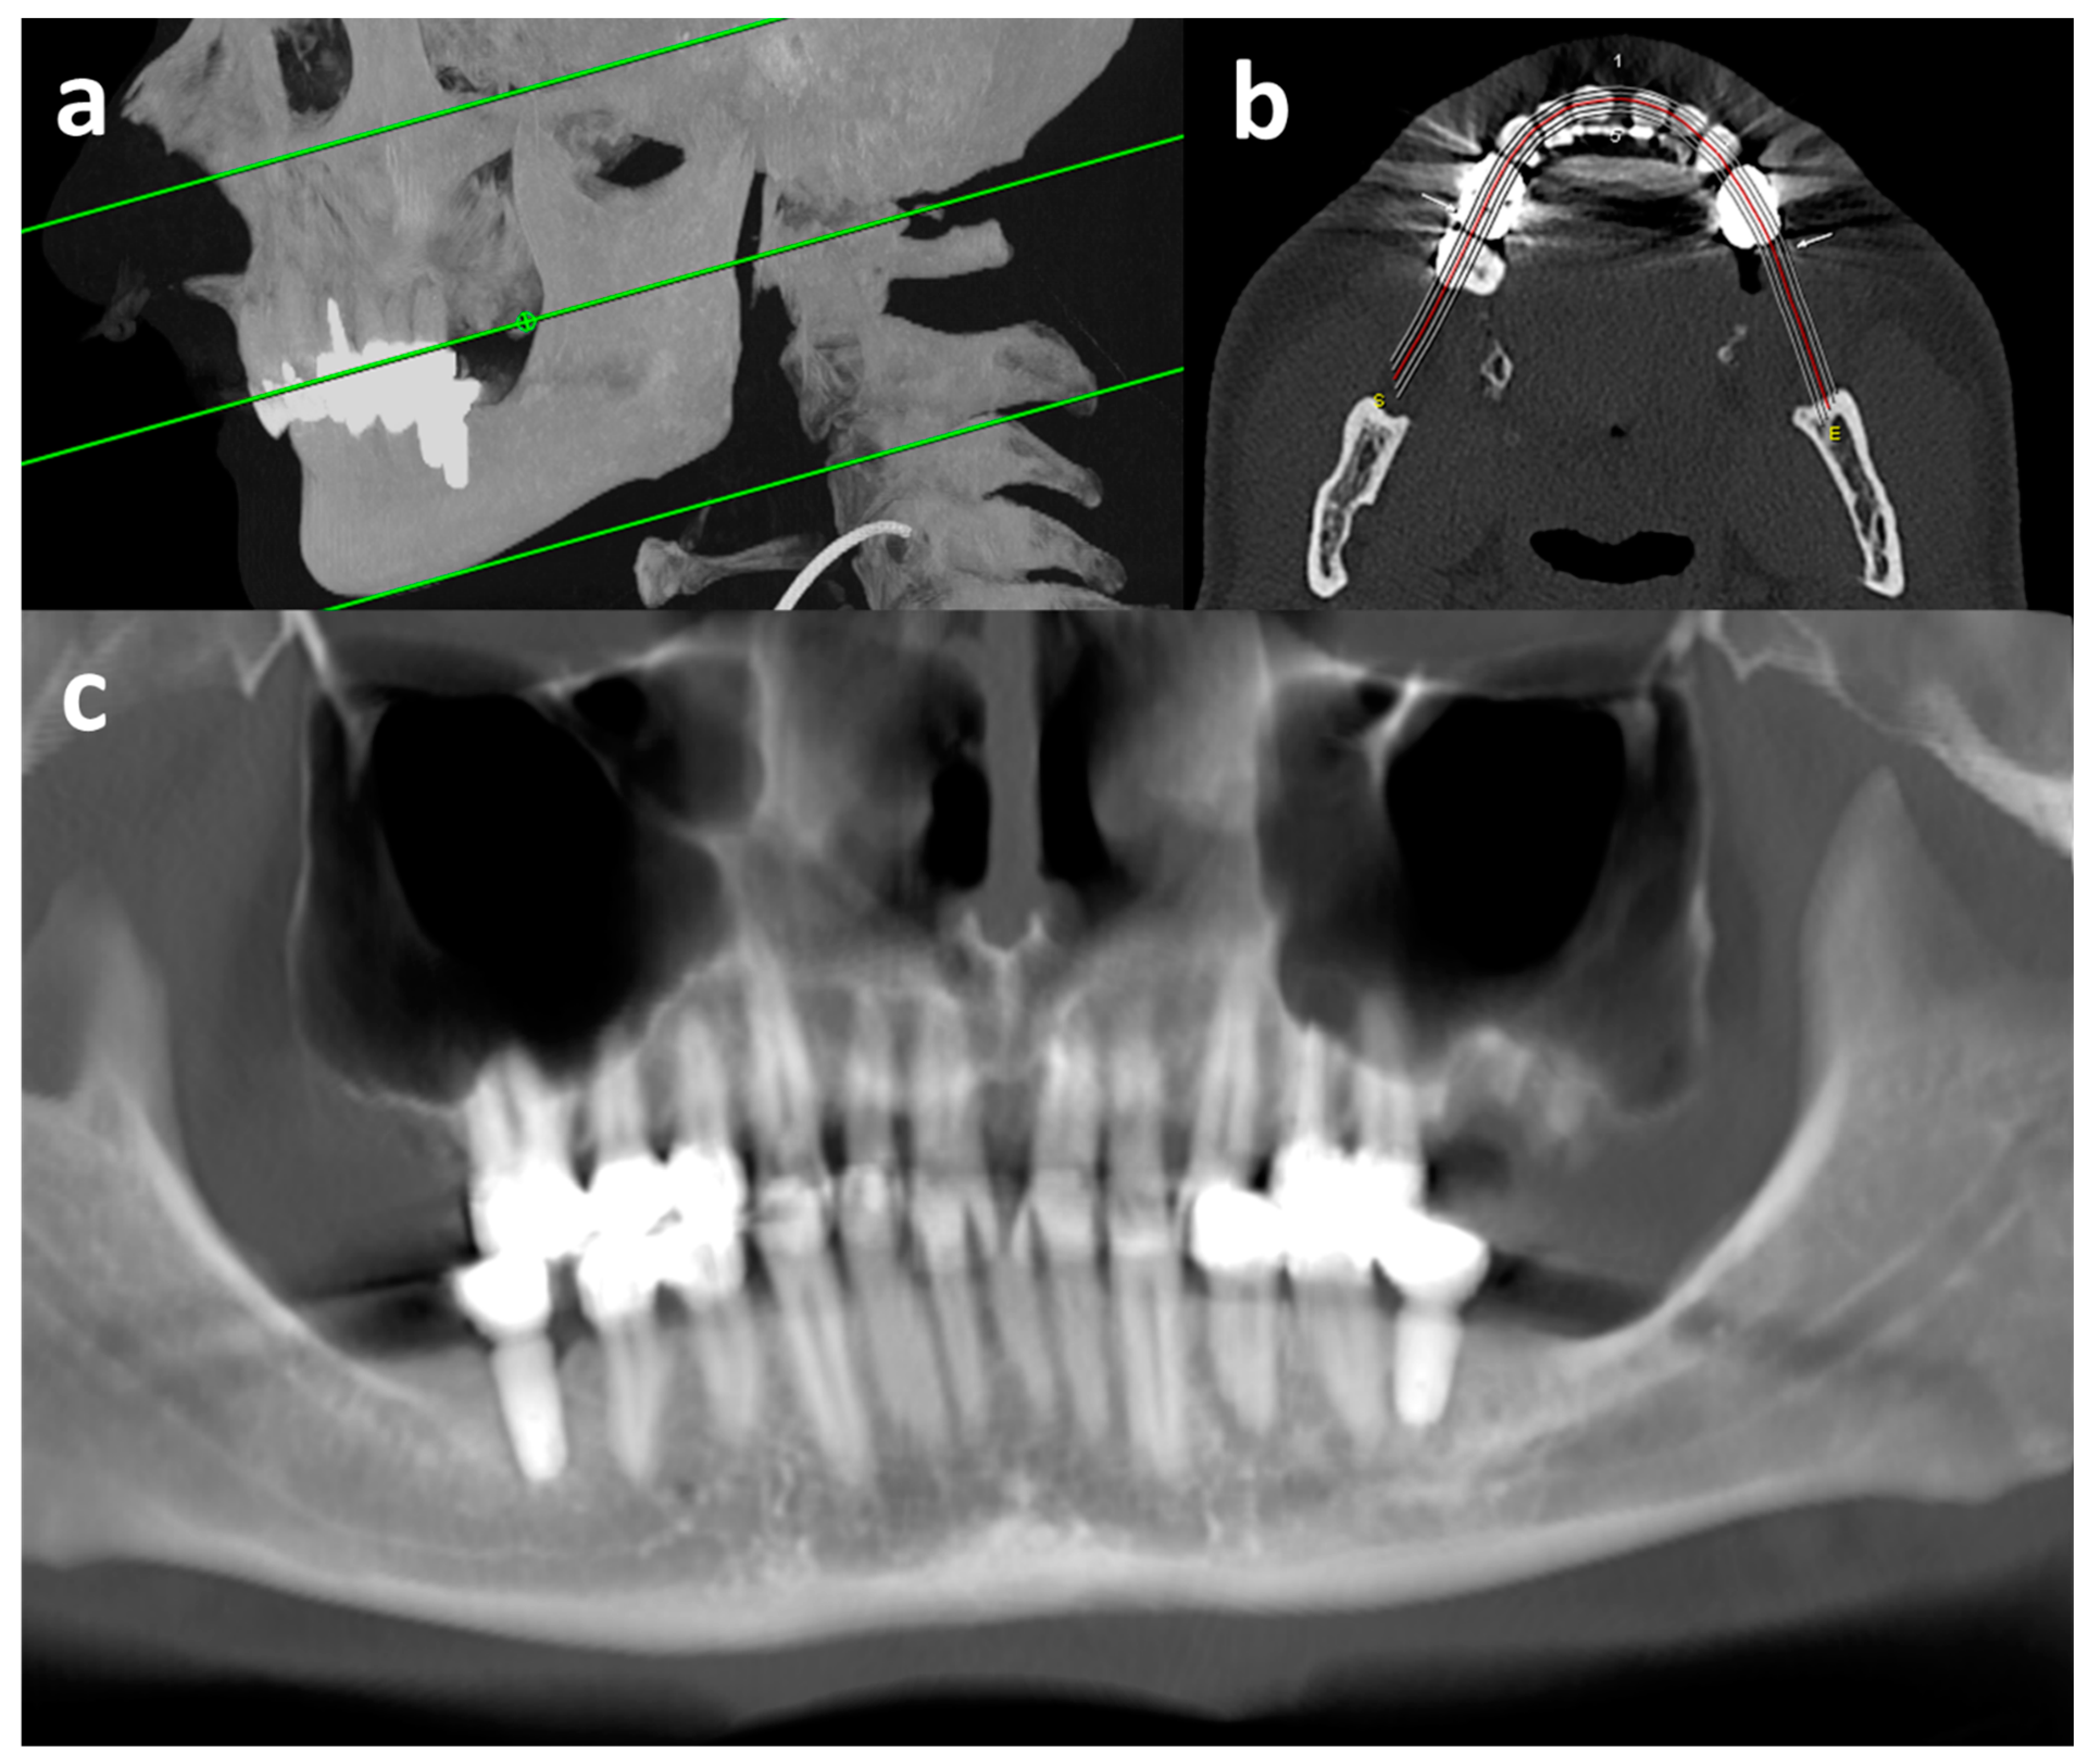

vOPGs were reconstructed (Figure 2 and Figure 3d) from the thinnest axial reconstructions available with a dedicated post-processing software (syngo.via, version VB60A HF03, Siemens Healthineers, Erlangen, Germany; workflow: dental). The creation of a vOPG lasted five to ten minutes. For this, a dentist manually set a plane parallel to the occlusal plane and drew a line along the occlusal surfaces of the maxillary and mandibular row of teeth. In order to create the vOPG, a maximum intensity projection at a six millimeter slice thickness was reconstructed perpendicular to this line (Figure 2). All vOPGs were reconstructed by the same dentist after prior training with an experienced radiologist.

Figure 2.

Reconstruction of vOPG from CT. Sagittal maximum intensity projection (a) for level selection of upper and lower limits and occlusal plain (green lines), para-axial plain (b) for contour selection of alveolar processes (red line: center of reconstruction), and margin selection of maximum intensity projection for the vOPG (outer white lines), and final vOPG (c) with very good image quality; CT = computed tomography examination; vOPG = virtual orthopantomogram.